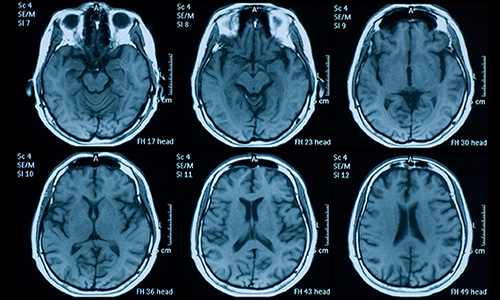

NIH (NINDS)   —   R21NS129147

Alberts, Jay

“The impact of exercise on subthalamic nucleus neural activity in Parkinson's disease”

Alberts JL: "System and Method to Facilitate Analysis of Brain Injuries and Disorders". US Patent No: 9,610,029; granted Apr 2017.